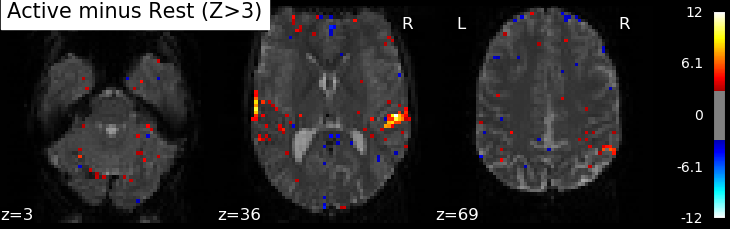

Correlations are computed separately at each voxel and a correlation map can be produced displaying the values of correlations (real numbers between -1 and +1) at each voxel. Generally, however, the maps presented in the papers report the significance of the correlations at each voxel, using T, Z or p values for the null hypothesis test of no correlation (see below). For example, the following figure displays a Z-map showing voxels responding to auditory events. Large (positive or negative) values are unlikely to be due to chance alone. The map is thresholded so that only voxels with a p-value less than 1/1000 are coloured.